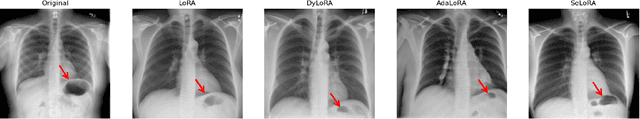

Abstract:The persistent challenge of medical image synthesis posed by the scarcity of annotated data and the need to synthesize `missing modalities' for multi-modal analysis, underscored the imperative development of effective synthesis methods. Recently, the combination of Low-Rank Adaptation (LoRA) with latent diffusion models (LDMs) has emerged as a viable approach for efficiently adapting pre-trained large language models, in the medical field. However, the direct application of LoRA assumes uniform ranking across all linear layers, overlooking the significance of different weight matrices, and leading to sub-optimal outcomes. Prior works on LoRA prioritize the reduction of trainable parameters, and there exists an opportunity to further tailor this adaptation process to the intricate demands of medical image synthesis. In response, we present SeLoRA, a Self-Expanding Low-Rank Adaptation Module, that dynamically expands its ranking across layers during training, strategically placing additional ranks on crucial layers, to allow the model to elevate synthesis quality where it matters most. The proposed method not only enables LDMs to fine-tune on medical data efficiently but also empowers the model to achieve improved image quality with minimal ranking. The code of our SeLoRA method is publicly available on https://anonymous.4open.science/r/SeLoRA-980D .